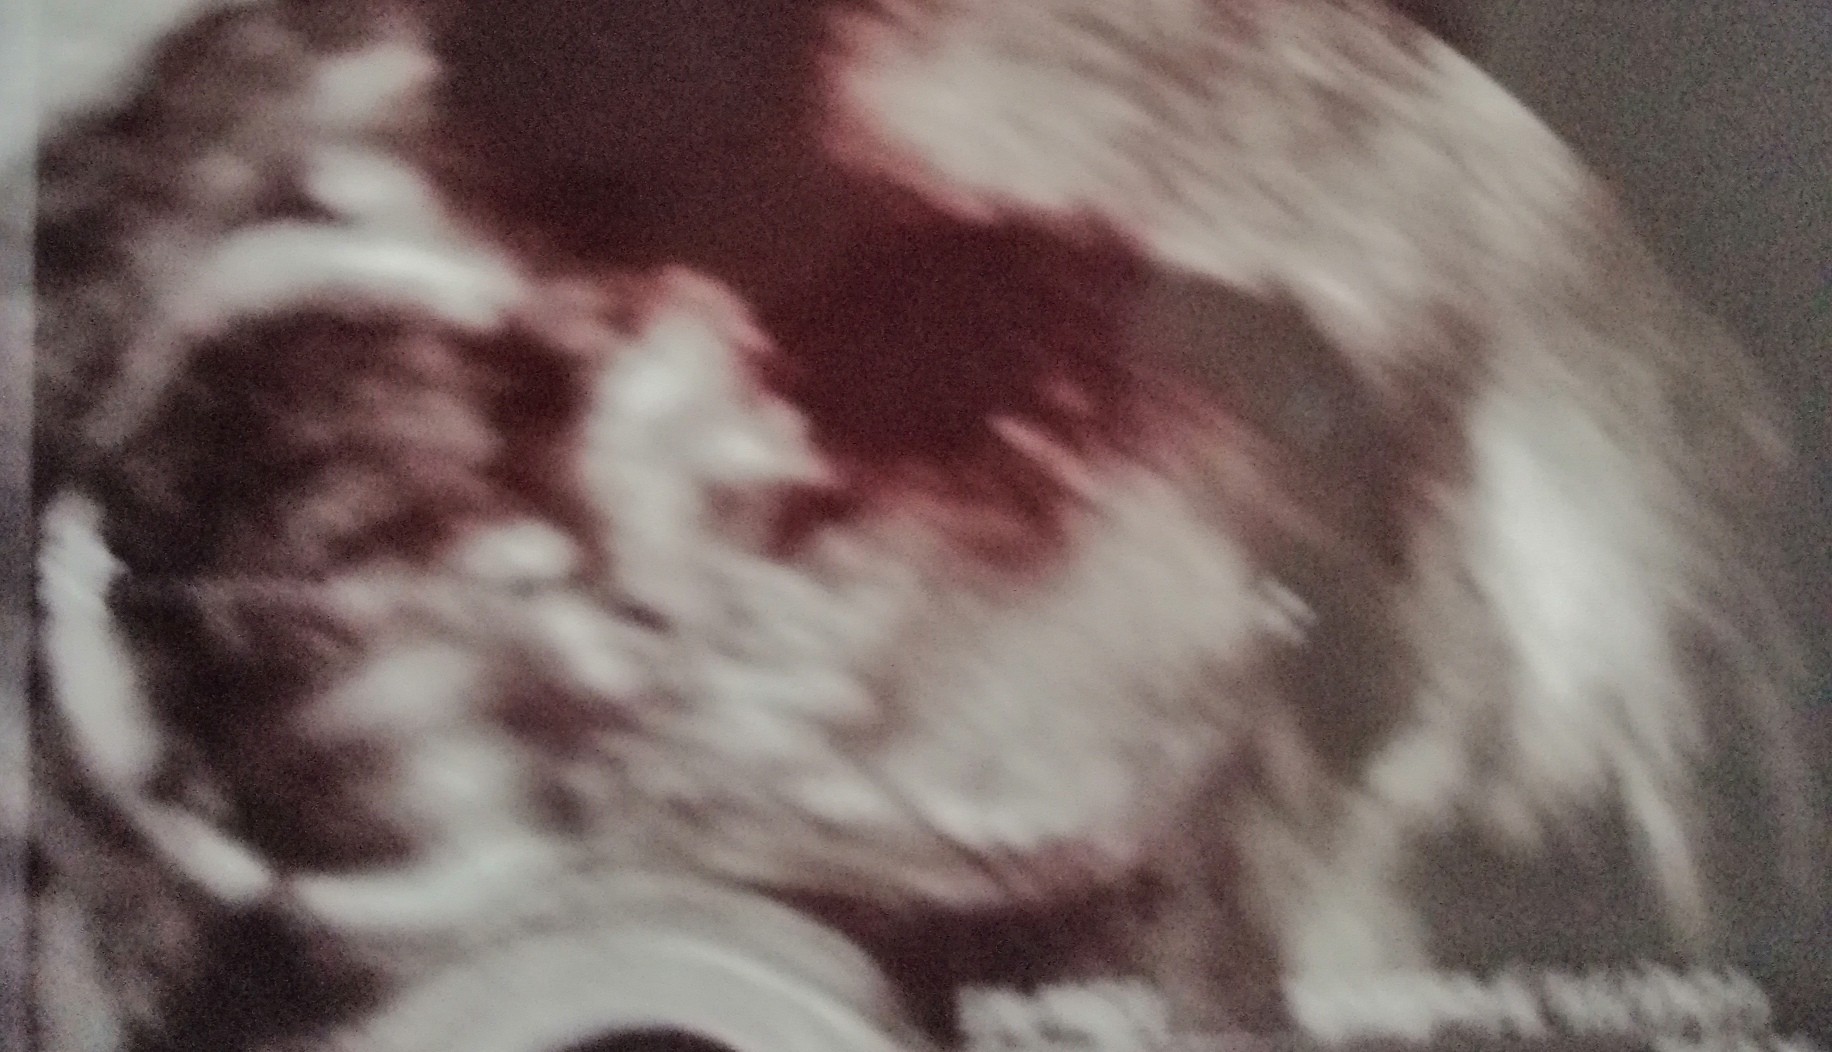

A u mnie? Niby oczywiste, ale jednak lekarz stwierdził, ze to tylko „na dzień dzisiejszy”, wiec co widzicie? Czy może z tego wyjść dziewczynka?

• C483F985-90F0-4A13-9F10-E067CAD4D09A.jpeg

C483F985-90F0-4A13-9F10-E067CAD4D09A.jpeg

1,5 MB · Wyświetleń: 257